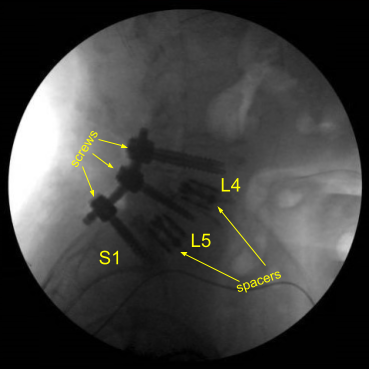

Expandable titanium interbody spacers, 15-degree lordotic at L5-S1 and 10-degree lordotic at L4-5, were placed under fluoroscopic guidance and expanded to proper fit. There was partial subsidence of the interbody spacer at L5-S1 into the L5 body, but it was secured and tight fit and imaging showed midline positioning.

CT scan was then obtained (shown above) which showed correct positioning of all the hardware. Neuromonitoring signals were stable. The wound was irrigated copiously. Bilateral transverse processes were decorticated for posterolateral arthrodesis from L4 to S1.

Precut titanium rods were contoured with rod benders and placed across the screw tulips from L4 to S1and secured with locking caps which were all final tightened with a torque and anti torque device. Final AP and lateral x-rays showed correct and complete hardware implantation.

Post Op X-ray